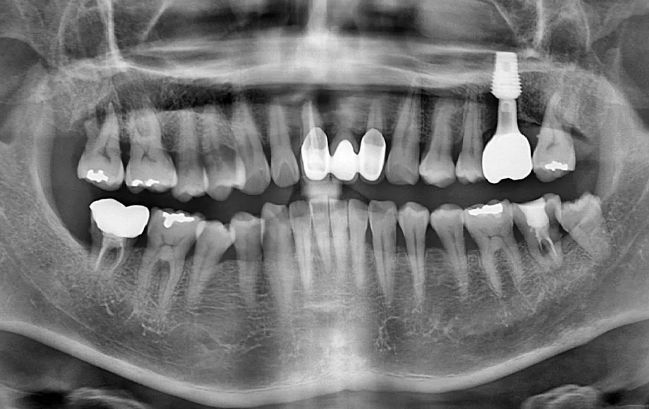

50대 남성, 앞니 임플란트